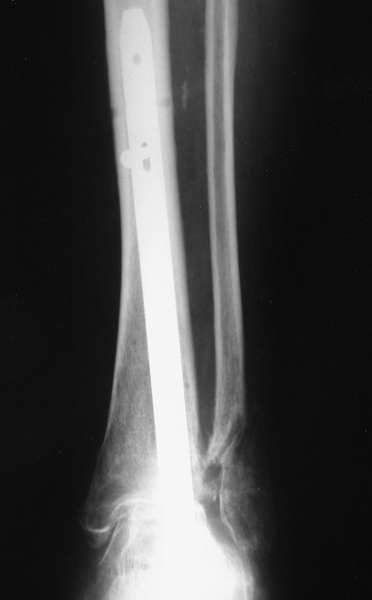

Мы бы сделали тоже самое с остатками лодыжек, но артродез, который безусловно показан, выполнили бы закрыто блокируемым штифтом (типа DFN) через пятку. Опороспособность восстановится сразу, артродез (рентгенологический) наступит месяцев через 4-6.

Можно: 65-летняя пациентка, оперирована по поводу несросшегося в гипсе перелома лодыжек с патологической вальгусной установкой стопы и выраженным нарушением опрной функции. Оперирована через 6 месяцев после травмы. Рентгенограммы через 4 месяца после операции.

Уважаемый А.Семенистый. Складывается впечатление, что вы выполнили трехсуставный артродез, уж больно длинные блокирующие винты. Не мешают ли они пациентке при ходьбе?

Да конечно винты длинноваты! Мешают ли ходить? Во всяком случае субьективно пациентка удовлетворена. Ходит, естевственно, хуже чеи до травмы, но намного лучше, чем до операции.